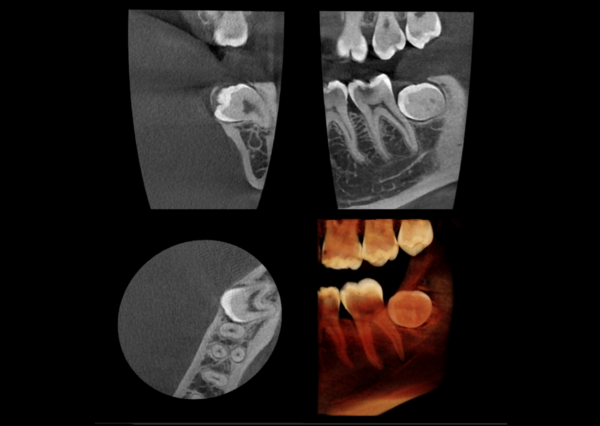

FOV nhỏ (4×5, 5×5): Tối ưu cho Nội nha, độ phân giải cực cao để tìm ống tủy phụ, đánh giá nứt gãy.

Phát hiện các tổn thương nội nha, nang nứt chân răng mà X-quang thường bỏ sót.

Xác định rõ ràng đường đi của ống thần kinh răng dưới (IAN) và ranh giới xoang hàm.